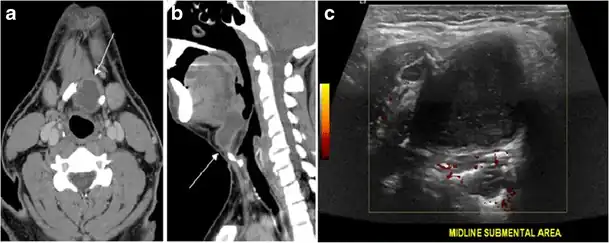

Fig. 7. A 51-year-old female patient post total thyroidectomy for PTC with elevated thyroglobulin measurement. an Axial non-enhanced CT scan of the neck at the level of the thyroid bed demonstrates a well-defined, rounded, homogenously dense soft tissue situated between the trachea and left internal jugular vein (white arrow). b Transverse ultrasound image of the neck demonstrates a well-defined, homogeneous, hypoechoic soft tissue nodule measuring 6 mm (white arrow) with no detected micro-calcifications. Biopsy showed a predominantly residual normal thyroid tissue with micro-foci of PTC.[1] -